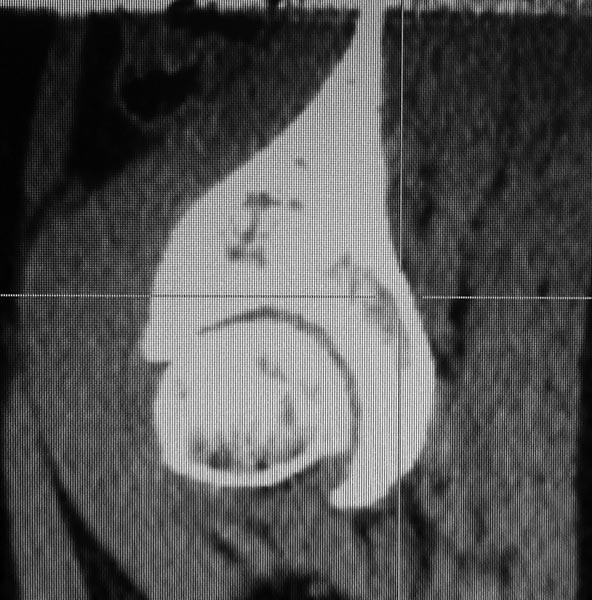

Доброго времени суток уважаемые коллеги посоветуйте как поступить в

данной ситуации.Больная 48 лет, работает рентген лаборантом. В течение

трех лет отмечает боли в левом тазобедренном суставе после работы и в

ночное время. Консервативное лечение без эффекта. Ходит с едва заметной

хромотой. Движения в лев Т/беддр.суставе сгибание 110

разгибание 5 Ротационные нар 40 кнутри 30 гр внутренн.ротация резко

болезненна. К травматологам не обращалась до сего момента - боится

эндопроезирования! На КТ выявлен Impingement передне- верхнего края

вертлужной впадины с головкой бедра. Из кагого доступа

лучше убрать? Или вообще не убирать?